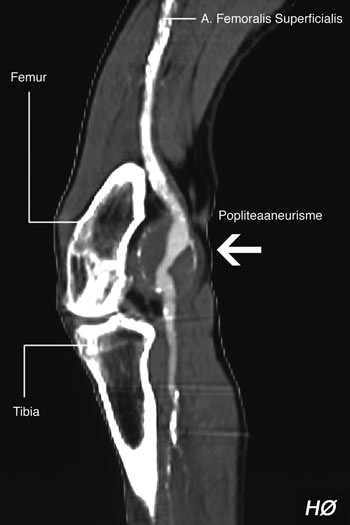

En 77 år gammel mann var gjennom en 12-årsperiode operert for aneurismer på bukaorta, bekkenarterier og arterier i lysker og knehaser. Han ble innlagt med dyp venetrombose i venstre lår og behandlet med warfarin. På grunn av økende hevelse og smerter i låret ble han overflyttet til Aker universitetssykehus 20 dager etter at symptomene debuterte. Etter ytterligere tre dagerble han operert med incisjon og evakuering av 800 ml illeluktende, brunfarget puss og nekrotisk vev. Vi fant også et rumpert aneurisme på venstre a. poplitea (fig 1). På høyre side var det likeledes et aneurisme, men det var ikke rumpert (fig 2). Infisert femoropopliteal bypass ble fjernet og erstattet med en ny bypass under kneleddet med snudd autolog vene.

Dupleksultralydundersøkelse av venstre knehase viste et aneurisme i a. poplitea med god blodstrømningshastighet i lår- og leggarterie, samt dyp venetrombose. CT av begge knærne viste bilaterale popliteaaneurismer med diameter 2,5 – 3,0 cm. Ingen ruptur ble registrert. Pga. mistanke om erysipelas fikk pasienten dikloksacillin og penicillin intravenøst.

På dag 17 ble det foretatt sirkulasjonsfysiologisk utredning. Dupleksundersøkelse viste et rumpert popliteaaneurisme med blødning ut av aneurismesekken på venstre side.